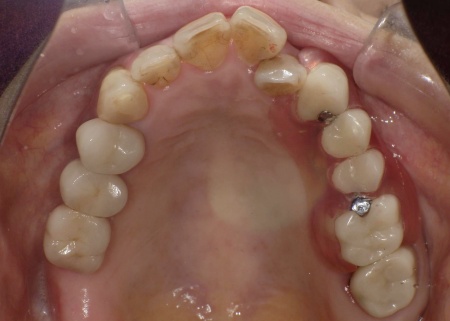

70代女性 歯根が折れた歯を抜いて金属バネを使用しない部分入れ歯で補った症例

拝見したところ、左上の歯(第2小臼歯)が欠損しており、この部分を補うために、両隣の歯を土台として橋を渡すように連結した被せ物「ブリッジ」が装着されていました。

今回は審美性を考慮して、金属のバネではなく樹脂の留め具で固定する部分入れ歯「ノンクラスプデンチャー」を提案し、同意いただきました。

ノンクラスプデンチャーの留め具は歯茎に近い色をしているため、目立ちにくいのが特徴です。

また、体調が回復した時点でインプラント治療へ移行する可能性もふまえ、ノンクラスプデンチャーは手術部位を圧迫しにくく、調整がしやすい設計で作製することになりました。

3ヶ月間の経過観察後、傷が治癒したことが確認できたため、ノンクラスプデンチャーを作製するための型取りを行いました。

また、噛み合わせの記録を取ったり、周囲の歯に馴染む色調の人工歯を選んだりなど、患者様によりぴったりと合う入れ歯に仕上げています。

約3週間後、完成した入れ歯を装着し、使用感や見た目に問題がないことを確認して、治療を終了しました。